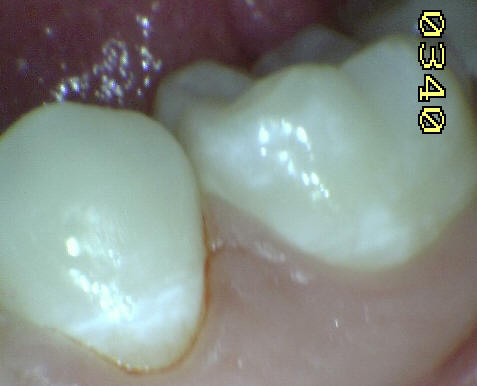

Casos clínicos de

fluorosis leve. |

Esmalte liso, traslucido y

cristalino, con finas bandas horizontales de color

blanquecino. |

Esmalte liso, traslúcido y

cristalino acompañado con gruesas líneas

horizontales blanquecinas. |

Las manchas opacas por fluorosis leve deben

diferenciarse con los códigos1 y 2 de ICDAS. En las

fluorosis el esmalte aparece brillante; mientras que

en el proceso de caries se observa un blanco aspecto

de tiza. (sin brillo) |